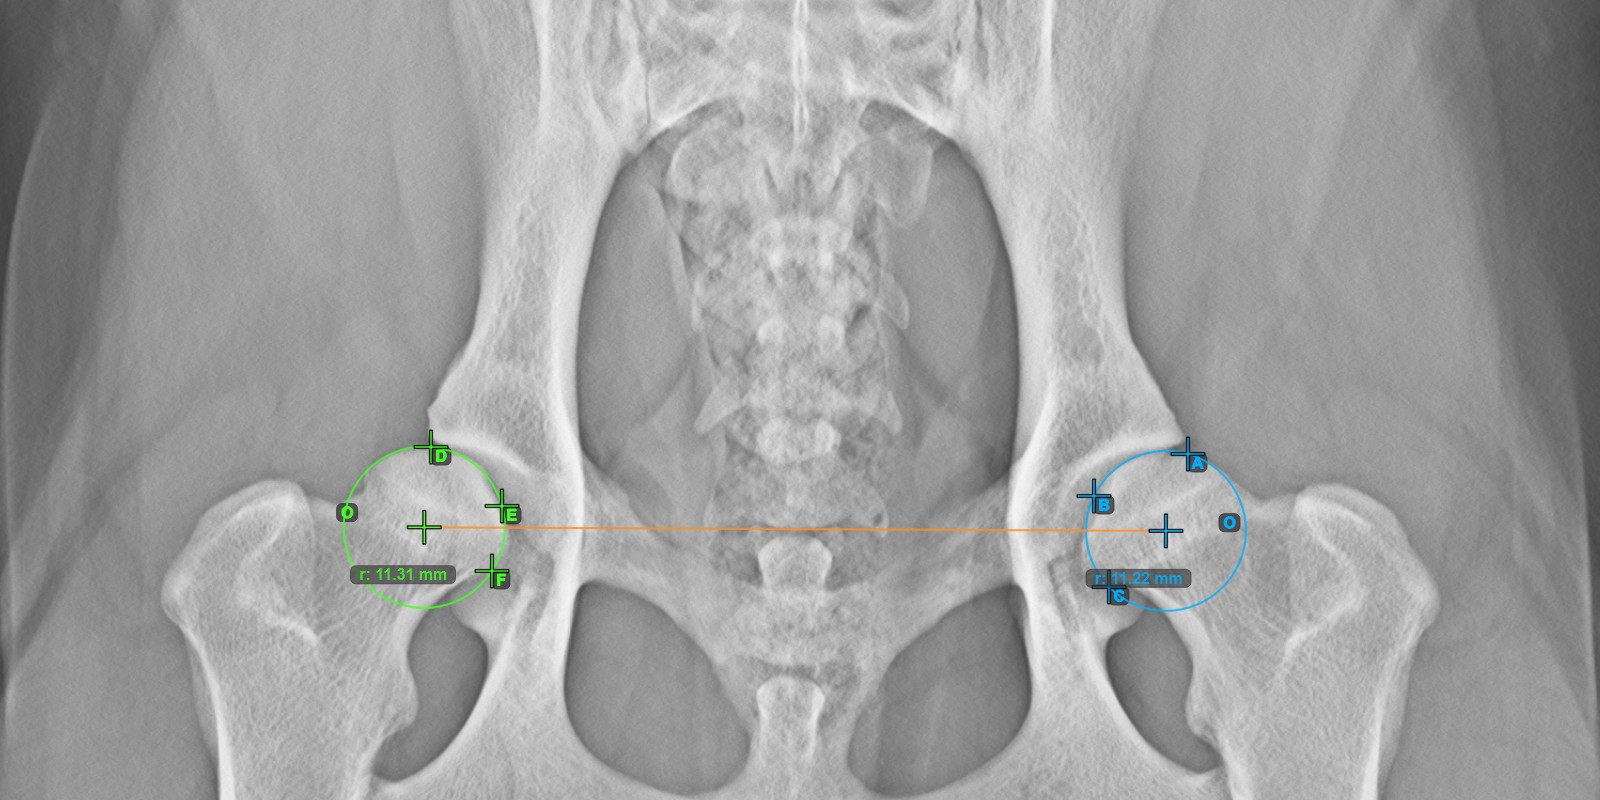

Calculate the right Norberg Angle measurement by marking a line on the effective edge of the right Acetabularis bone, completing the entire advanced measurement.

Mark a point near the right Caput Femoris and drag it along the effective edge of the right Acetabularis bone, forming the terminal side of the right Norberg Angle.

The drawn line must be a tangent to the effective edge of the right Acetabularis bone. The value and arc of the angle is automatically calculated.

The image below depicts the typical placement of the line and the calculated Norberg Angle measurement.